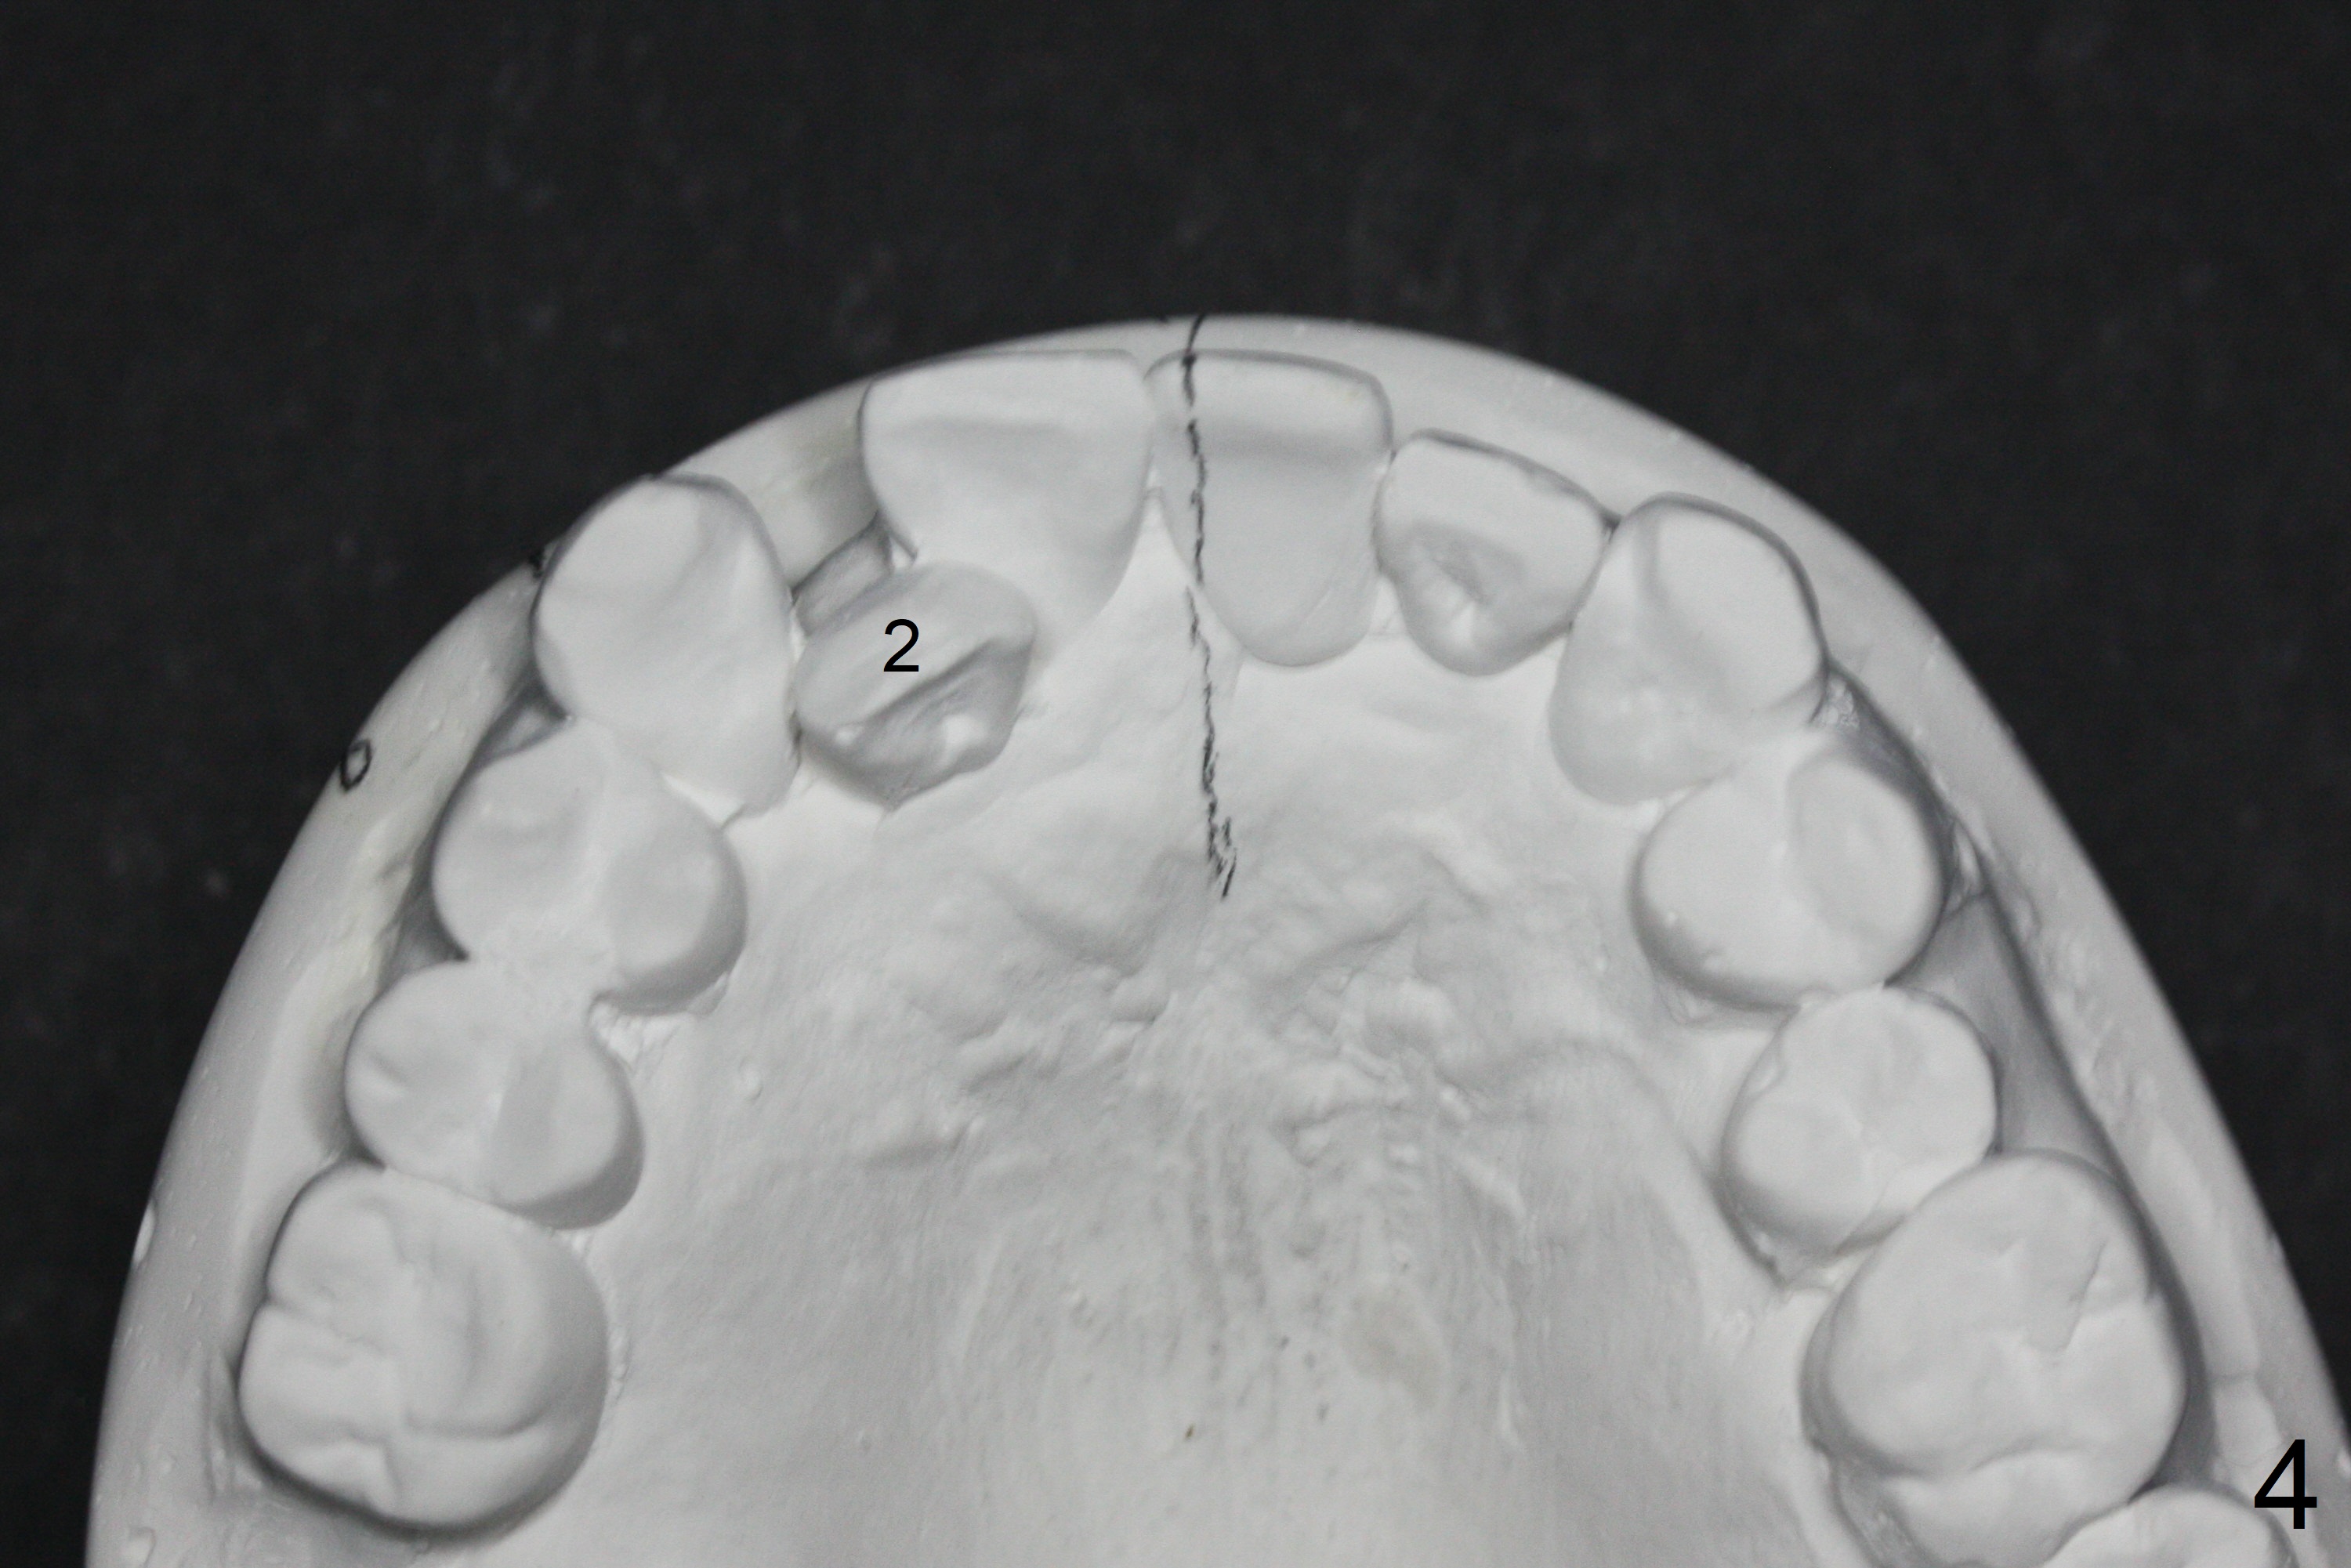

In spite of several warnings against orthodontic treatment for a 47-year-old man with chronic periodontitis, he requests it once more time before UL1 implant restoration. How to correct UR2 cross bite (Fig.1-4)? The number in pencil represents the width of each tooth in mm. For example the width of UR1 is 9 mm, whereas that of UL1 is 7 mm (Fig.2). The pencil line represents the facial midline and the upper dental midline. Ideally the UL1 should be moved distally ~ 1 mm.